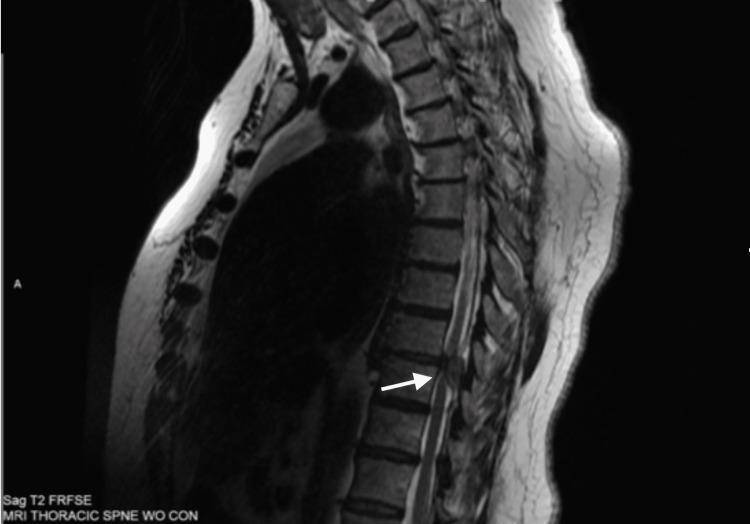

Guillain-Barré syndrome (GBS) is a rare autoimmune disorder that presents with neurological symptoms that can mimic other conditions. This mimicry can hide other important neurological diagnoses. Here, we present a rare case of thoracic myelopathy secondary to a sequestered dorsal epidural herniated disc fragment that initially presented with the classic findings of GBS. A 58-year-old female presented with progressing bilateral lower extremity weakness, paresthesias, and absent bilateral lower extremity deep tendon reflexes. Lumbar magnetic resonance imaging (MRI) findings were disproportionate to presentation, and lumbar puncture fluid analysis revealed clear, colorless fluid with albuminocytological dissociation. The patient was diagnosed with GBS and treated with a short course of intravenous steroids followed by intravenous immunoglobulin. The patient later developed new-onset ulnar distribution paresthesias, lower extremity spasticity, constipation, and urinary retention that caused a decline in functional progress. Further investigation prompted evaluation with cervical and thoracic MRIs, which revealed a left dorsal epidural lesion at the T9-T10 level causing severe cord compression. The patient was definitively treated with a T9-T10 laminectomy and excision of the offending lesion. Pathology revealed collagenous tissue with fibroblastic proliferation, consistent with a sequestered fragment of the herniated intervertebral disc. The patient was further treated with both acute and subacute rehabilitation. She was eventually discharged home and was able to ambulate independently with a walker. Dependency on positive albuminocytological dissociation in cases of potential GBS can lead to errors in diagnostic accuracy and delay appropriate treatment. Clinicians should remain mindful that GBS is a diagnosis of exclusion and MRI of the entire spine should be considered when the diagnosis of GBS is uncertain.

吉兰 - 巴雷综合征(GBS)是一种罕见的自身免疫性疾病,其神经系统症状可能与其他病症相似。这种相似性可能掩盖其他重要的神经系统诊断。在此,我们报告一例罕见的因隐匿性背侧硬膜外椎间盘突出碎片继发的胸段脊髓病,该病例最初表现为吉兰 - 巴雷综合征的典型症状。一名58岁女性出现双侧下肢进行性无力、感觉异常,双侧下肢深腱反射消失。腰椎磁共振成像(MRI)结果与临床表现不符,腰椎穿刺脑脊液分析显示清亮、无色液体,存在蛋白细胞分离现象。该患者被诊断为吉兰 - 巴雷综合征,并接受了短期静脉注射类固醇治疗,随后静脉注射免疫球蛋白。患者后来出现新发的尺侧感觉异常、下肢痉挛、便秘和尿潴留,导致功能进展下降。进一步检查促使进行颈椎和胸椎MRI评估,结果显示T9 - T10水平左侧硬膜外病变,导致严重脊髓受压环。患者最终接受了T9 - T10椎板切除术并切除病变。病理显示胶原组织伴有成纤维细胞增生,符合椎间盘突出的隐匿性碎片。患者进一步接受了急性和亚急性康复治疗。她最终出院回家,能够借助助行器独立行走。在潜在吉兰 - 巴雷综合征病例中依赖阳性蛋白细胞分离可能导致诊断准确性错误并延误适当治疗。临床医生应牢记,吉兰 - 巴雷综合征是一种排除性诊断,当吉兰 - 巴雷综合征诊断不确定时,应考虑对整个脊柱进行MRI检查。